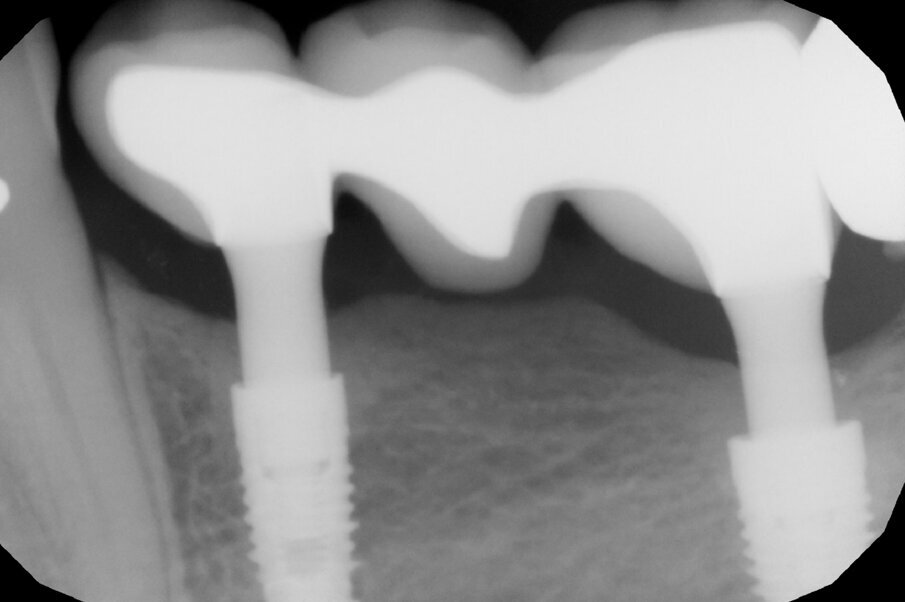

After 70 days, radiographic control was performed and the healing abutments were replaced with two easy abutments directly in order to comply with the one abutment, one time protocol (Fig. 4). The abutments were torqued to 30 Ncm according to the implant’s prosthetic protocol. This is necessary for the activation of the conical coupling between implant and abutment and for a sterile connection that prevents micro-movements and bacterial infiltration between implants and abutments in the sub-crestal area and the resulting bone resorption. Thereafter, we took a polyether impression on snap-on copings directly inserted on the abutments and fabricated a traditional cemented metal–ceramic bridge. In the following months, the patient initially underwent regular check-ups and professional hygiene, but thereafter kept extending the check-up times and neglecting her oral hygiene.

A further radiographic check was carried out seven years after the implants had been placed and showed growth of the bone level and the formation of a curved bone profile to support the interdental papillae, which is typical of natural teeth (Figs. 6a &b). Caries occurred under the crown of tooth #37, but the patient did not wish to have it treated. Upon physical examination, the soft tissue appeared stable and of excellent trophism.

After nine years, a new radiograph was performed which highlighted how the scallop had not only been maintained but even remodelled (Figs. 7a & b). The supra-implant bone appearance around the abutments presented a hyperdense and extreme continuity with the abutment neck, despite the non-punctual hygienic maintenance, highlighted by the state of the soft tissue and by the caries affecting tooth #37, then in the terminal stage (Figs. 8 & 9). After removal of the bridge, we tried probing, but it was absolutely impossible owing to the thickness of the soft tissue.